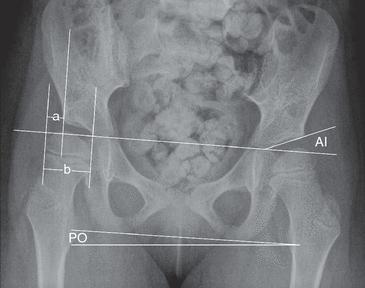

- Chụp X quang khớp háng thẳng và đo Phần trăm Di lệch (MP, Migration percentage)

- Đo Phần trăm Di lệch: Phần trăm di lệch = A/B × 100%